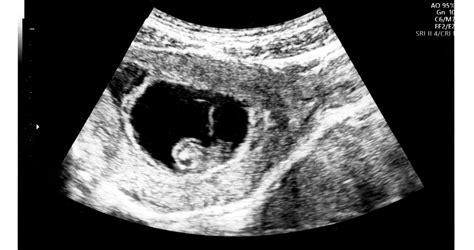

A modern ultrahangos készülékek meglehetősen nagy segítséget nyújtanak ebben a tekintetben, de a legtöbb orvos a terhesség idejének megállapításában és a szülés várható idejének kiszámításában a nő utolsó menstruációs ciklusának első napját fogja figyelembe venni. Ugyanis, hacsak a nő szexuális élete korlátozott volt, vagy valamilyen termékenységi kezelést kapott, a fogamzás pontos idejének meghatározása nem lehetséges. Az első ultrahangos vizsgálat során általában a nőgyógyász megerősíti a menstruációs ciklus alapján kiszámított teherbeesés időpontját, és amennyiben a kettő között jelentős eltéréseket tapasztal, további vizsgálatokra lehet szükség. Az ultrahangos vizsgálat általában a megtermékenyülés utáni 23-25.-ik napon tudja először kimutatni a terhességet (ekkor a magzat nem látszik még, csak a petezsák megléte). Az első ultrahangos szűrést általában a terhesség 12. hetében végzik el.